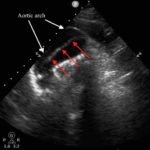

We present a case of a 51-year-old previously healthy man who presented to the ED complaining of chest pain that had resolved prior to arrival, and a mild headache. His vital signs were notable for hypotension, but physical exam was unremarkable. Chest x-ray revealed a borderline widened mediastinum. A standard ETTE was within normal limits, but additional SSNV demonstrated a dissection flap in the aortic arch. The patient was taken to the operating room for surgical repair 75 minutes after the ED ultrasound was performed; the operation was successful, and the patient was discharged to home post-operatively with good outcome.

Standard ETTE has limited ability to visualize the ascending aorta and aortic arch. Addition of SSNV allows visualization of these structures and may improve diagnostic accuracy and time to diagnosis of proximal aortic dissection.